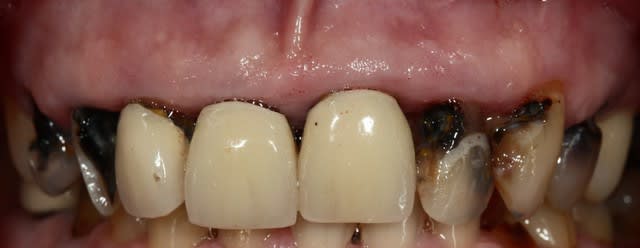

Tiens un cas s'approchant du tiens Chicot...comme je suis mauvais en Endo, j'essaye d'en faire le moins possible.

J'ai gardé vivant ce que je pouvais.

Le cas à 3 ans... RAS, j'ai vu la patiente il y a 2 mois.